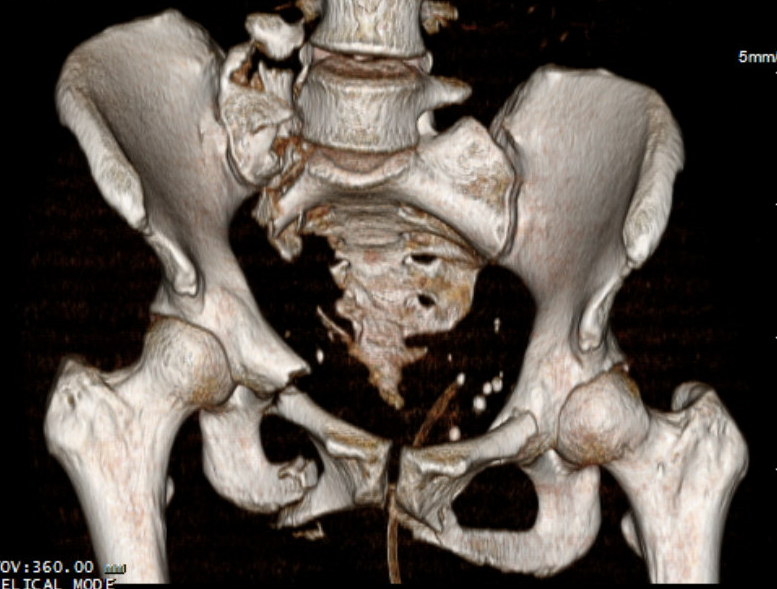

Vert shear CTVertical shear fixation

vert shearvert shear